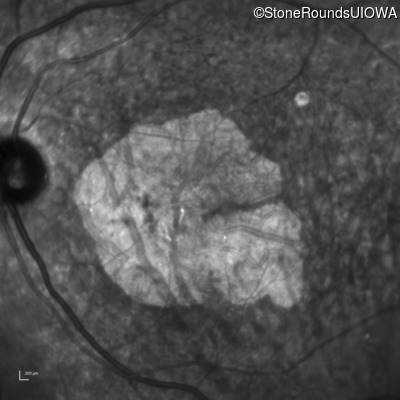

AR Stargardt Disease (IIA)

AR Stargardt Disease

ABCA4

Gly607Arg GGG>AGG

IVS30+1321 A>G

AR

Disease:

Gene:

Allele 1:

Allele 2:

Inheritance: